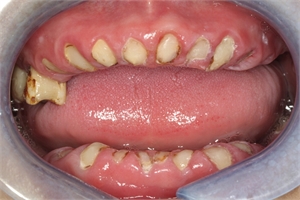

Teeth roots retained in the mouth jawbone

Every tooth has the same basic anatomy, with a crown that is visible above the gum line and roots below to anchor the tooth to the jawbone. Teeth in the front of the mouth have one root, with more roots per tooth moving back to the molars. When attached to a healthy tooth, root tips cause no problems whatsoever. But if a tooth is lost or fractured through trauma or decay, fragments of the root or roots may be retained in the jawbone. It is even more common for molars because they can have up to four tooth roots. If a root tip fracture occurs, the clinician must decide to either leave it or attempt removal. Here is what patients need to know about retained tooth roots and treatment options.

Retained tooth roots are either found incidentally on x-rays or are fractured during extraction procedures. But the decision to remove retained root fragments needs to be made on a case-by-case basis. The length, position, mobilization, and pulpal status of the retained root along with an adequate closure of the socket margins all contribute to the possible outcome.